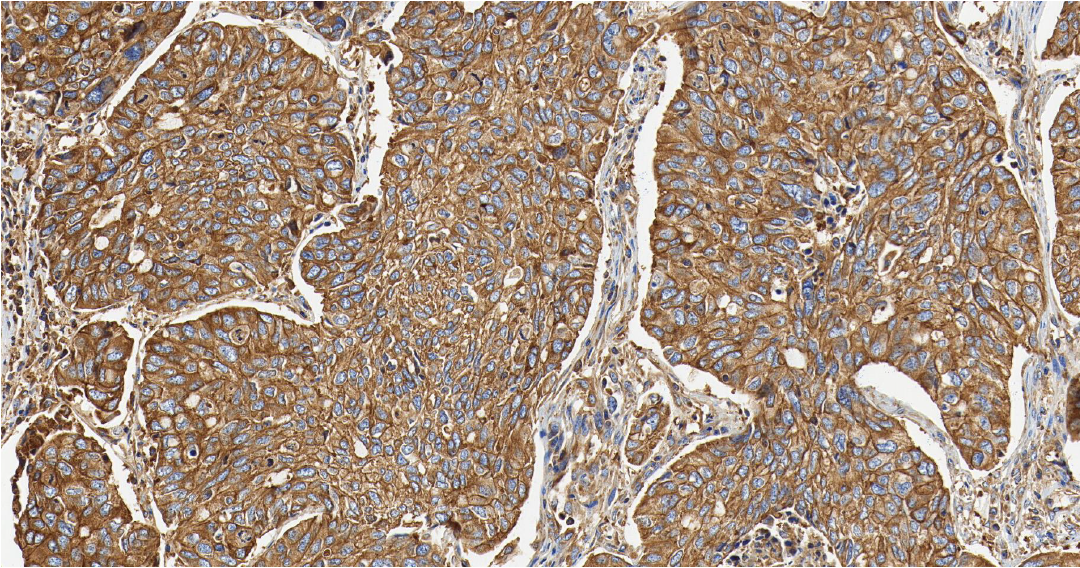

PD-L1

PD-L1—— 免疫检查点分子,属于 B7-CD28 免疫调节超家族。

定位: 细胞膜。

功能: PD-L1 是一种跨膜蛋白。其主要生理功能是在免疫突触中与免疫 T 细胞表面的 PD-1 受体结合,传递抑制性信号,通过抑制 T 细胞活化和增殖来发挥作用。

肿瘤细胞或肿瘤微环境中的免疫细胞会高表达 PD-L1,与浸润 T 细胞的 PD-1 结合,从而“关停” T 细胞的杀伤功能,实现免疫逃逸。 在非小细胞肺癌中,PD-L1 的表达水平是预测免疫检查点抑制剂疗效的关键生物标志物 [1] 。

图 1. 人肺癌组织的 PD-L1 免疫组化分析[2]。